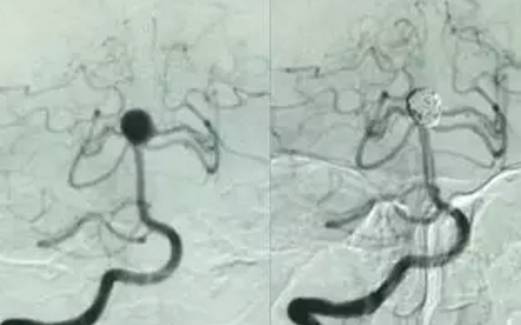

那么年仅32岁的梁女士为什么会突然发生这次意外呢?萧山中医院ICU副主任高劲松说,梁女士的初步诊断是因脑动脉瘤破裂导致广泛性蛛网膜下腔出血,因未及时被人发现,从而最终导致呼吸心跳骤停。